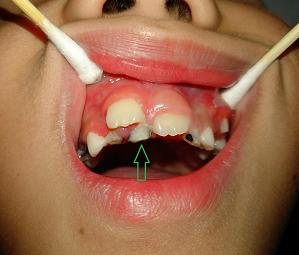

上颌牙乳牙滞留

下颌牙乳牙滞留

寒假期间,7岁的晨晨随父母来到湘雅常德医院口腔科门诊。当晨晨张开嘴,口腔科医生向峰医师发现患儿是典型的“双排牙”,专业上称之为乳牙滞留,在6~7岁的小朋友中特别常见。

随后几天,口腔科门诊也接诊了不少像晨晨这样的小患者。不少父母担心“双排牙”会影响孩子恒牙的生长发育,要求拔牙,而该拔哪颗、该留哪颗?这确实需要寻求专业口腔科医生的帮助,这就要求家长们得选择在正规医疗机构拍片后拔牙。